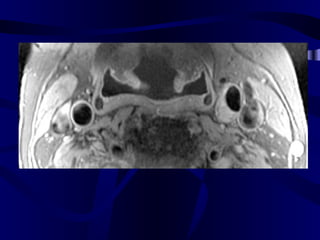

• 74.

Pre and Post-SPIOEnhanced Magnetic Resonance Imaging of ApoE K/O and Wild Type Mice: We used 4.7 tesla MRI unit in our study. After baseline MR imaging with respiratory gating, we injected 1mMolFe/kg super paramagnetic iron oxide to six ApoE deficient and two C57bl mice through the tail vein. Post-contrast MR imaging were performed in day 5 with the same parameters (TR=2.5 sec, TE=0.012 sec, FOV=6.6 cm, slice thickness=2.0mm, flip angle (orient)=trans, and matrices=256x256). We selected the aorta at the level of kidney for comparison of the baseline and post-contrast images.

Apo E deficientmice MRI SPIO experiment

MR Image ofAbdominal Aorta After SPIO Injection in Mouse Apo E deficient mouse C57B1 (control) mouse Before Injection After Injection (5 Days ) Dark (negatively enhanced) aortic wall, full of iron particles Bright aortic lumen and wall without negative enhancement and no significant number of iron particles